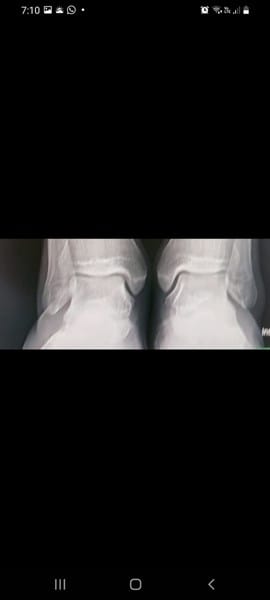

EndocrinologíaBiologíaHuesos y articulaciones manuel jose uribe pozo el 10 dic. 21 Puedo crecer 1 o 2 cm a mis 18 años recién cumplidos TENGO ESTAS RADIOGRAFÍAS QUISIERA SABER SI PUEDO CRECER 1 O 2 CM@ Seguir Siguiendo Dejar de seguir